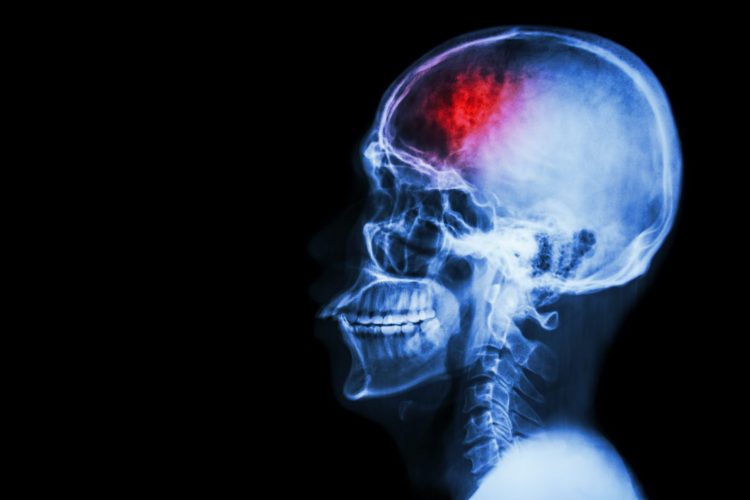

Retinoid X receptor could be targeted to improve recovery from stroke

Scientists conducted a pre-clinical trial in mice and showed that activating the retinoid X receptor (RXR) enhances the activity of phagocytic immune cells and aids recovery from stroke.